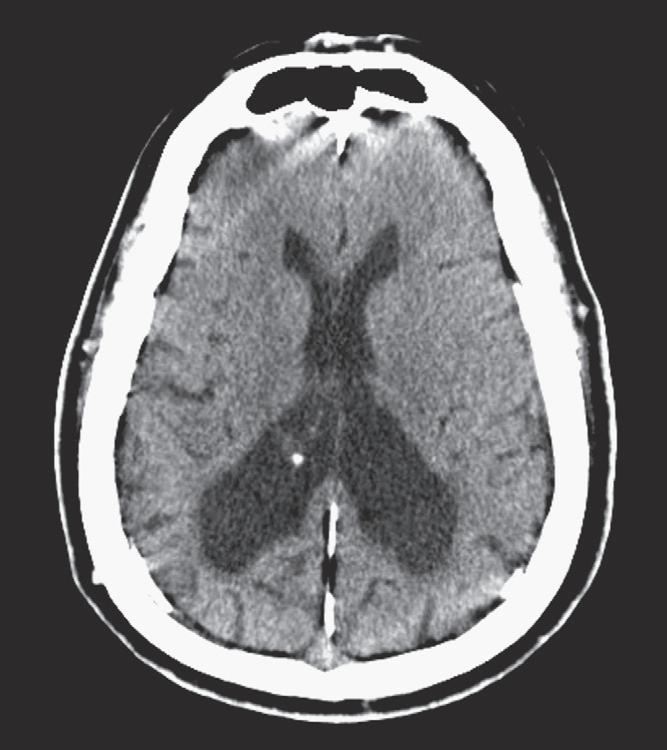

The word hemorrhage has Greek origins: the prefix haima-, meaning “blood,” and the suffix -rrhage, meaning “to gush or burst forth.” Incidence of ICH is approximately 25 to 30 per 100,000 adults in the United States, with a higher incidence in elderly hypertensive patients. ICH is typically more common in the African American and Asian populations. Bleeding may take place within the substance of the brain (intraaxial) or along the surface of the brain (extraaxial). Intraaxial hemorrhage implies parenchymal hemorrhage located in the cerebrum, cerebellum, or brainstem. Extraaxial hemorrhages include epidural, subdural, and subarachnoid hemorrhages, and intraventricular hemorrhage can be considered in this group as well. Hemorrhages can lead to different types of brain herniation, from direct mass effect and associated edema or development of hydrocephalus, causing significant morbidity and mortality.

The appearance of ICH on a CT scan can vary depending on the age of the hemorrhage and the hemoglobin level. The attenuation of blood is typically based on the protein content, of which hemoglobin contributes a major portion. Therefore the appearance of hyperacute/acute blood is easily detected on a CT scan in patients with normal hemoglobin levels (approximately 15 g/dL) and typically appears as a hyperattenuating mass. This appearance is typical because, immediately after extravasation, clot formation occurs with a progressive increase in attenuation over 72 hours as a result of increased hemoglobin concentration and separation of low-density serum. On the other hand, in anemic patients with a hemoglobin level less than 10 g/dL, acute hemorrhage can appear isoattenuating to the brain and can make detection difficult. Subsequently, after breakdown and hemolysis, the attenuation of the clot decreases until it becomes nearly isoattenuating to cerebrospinal fluid (CSF) by approximately 2 months. In the emergency setting, one should be aware of the “swirl” sign with an unretracted clot that appears to be hypoattenuating and resembles a whirlpool; this sign may indicate active bleeding and typically occurs in a posttraumatic setting. It is important to recognize this sign, because prompt surgical evacuation may be required. The amount of mass effect on nearby tissues will depend on the size and location of the hemorrhage, as well as the amount of secondary vasogenic edema that develops.

Intraventricular Hemorrhage

In the adult population, intraventricular hemorrhage (IVH) is typically caused by trauma. It can result from extension of a parenchymal hemorrhage into the ventricles or from redistribution of SAH. Primary IVH is uncommon and is usually caused by a ruptured aneurysm, an intraventricular tumor, vascular malformation, or coagulopathy (Fig. 1-8). Large IVHs are quite conspicuous on CT or MRI. They may occupy a majority of the ventricle(s) and may result in hydrocephalus and increased intracranial pressure. Small amounts of IVH may be difficult to detect; one must check carefully for dependent densities within the atria and occipital horns of the lateral ventricles. Normal choroid plexus calcifications in the atria of lateral ventricles, in the fourth ventricle, and extending through the foramina of Luschka should not be mistaken for acute IVH.